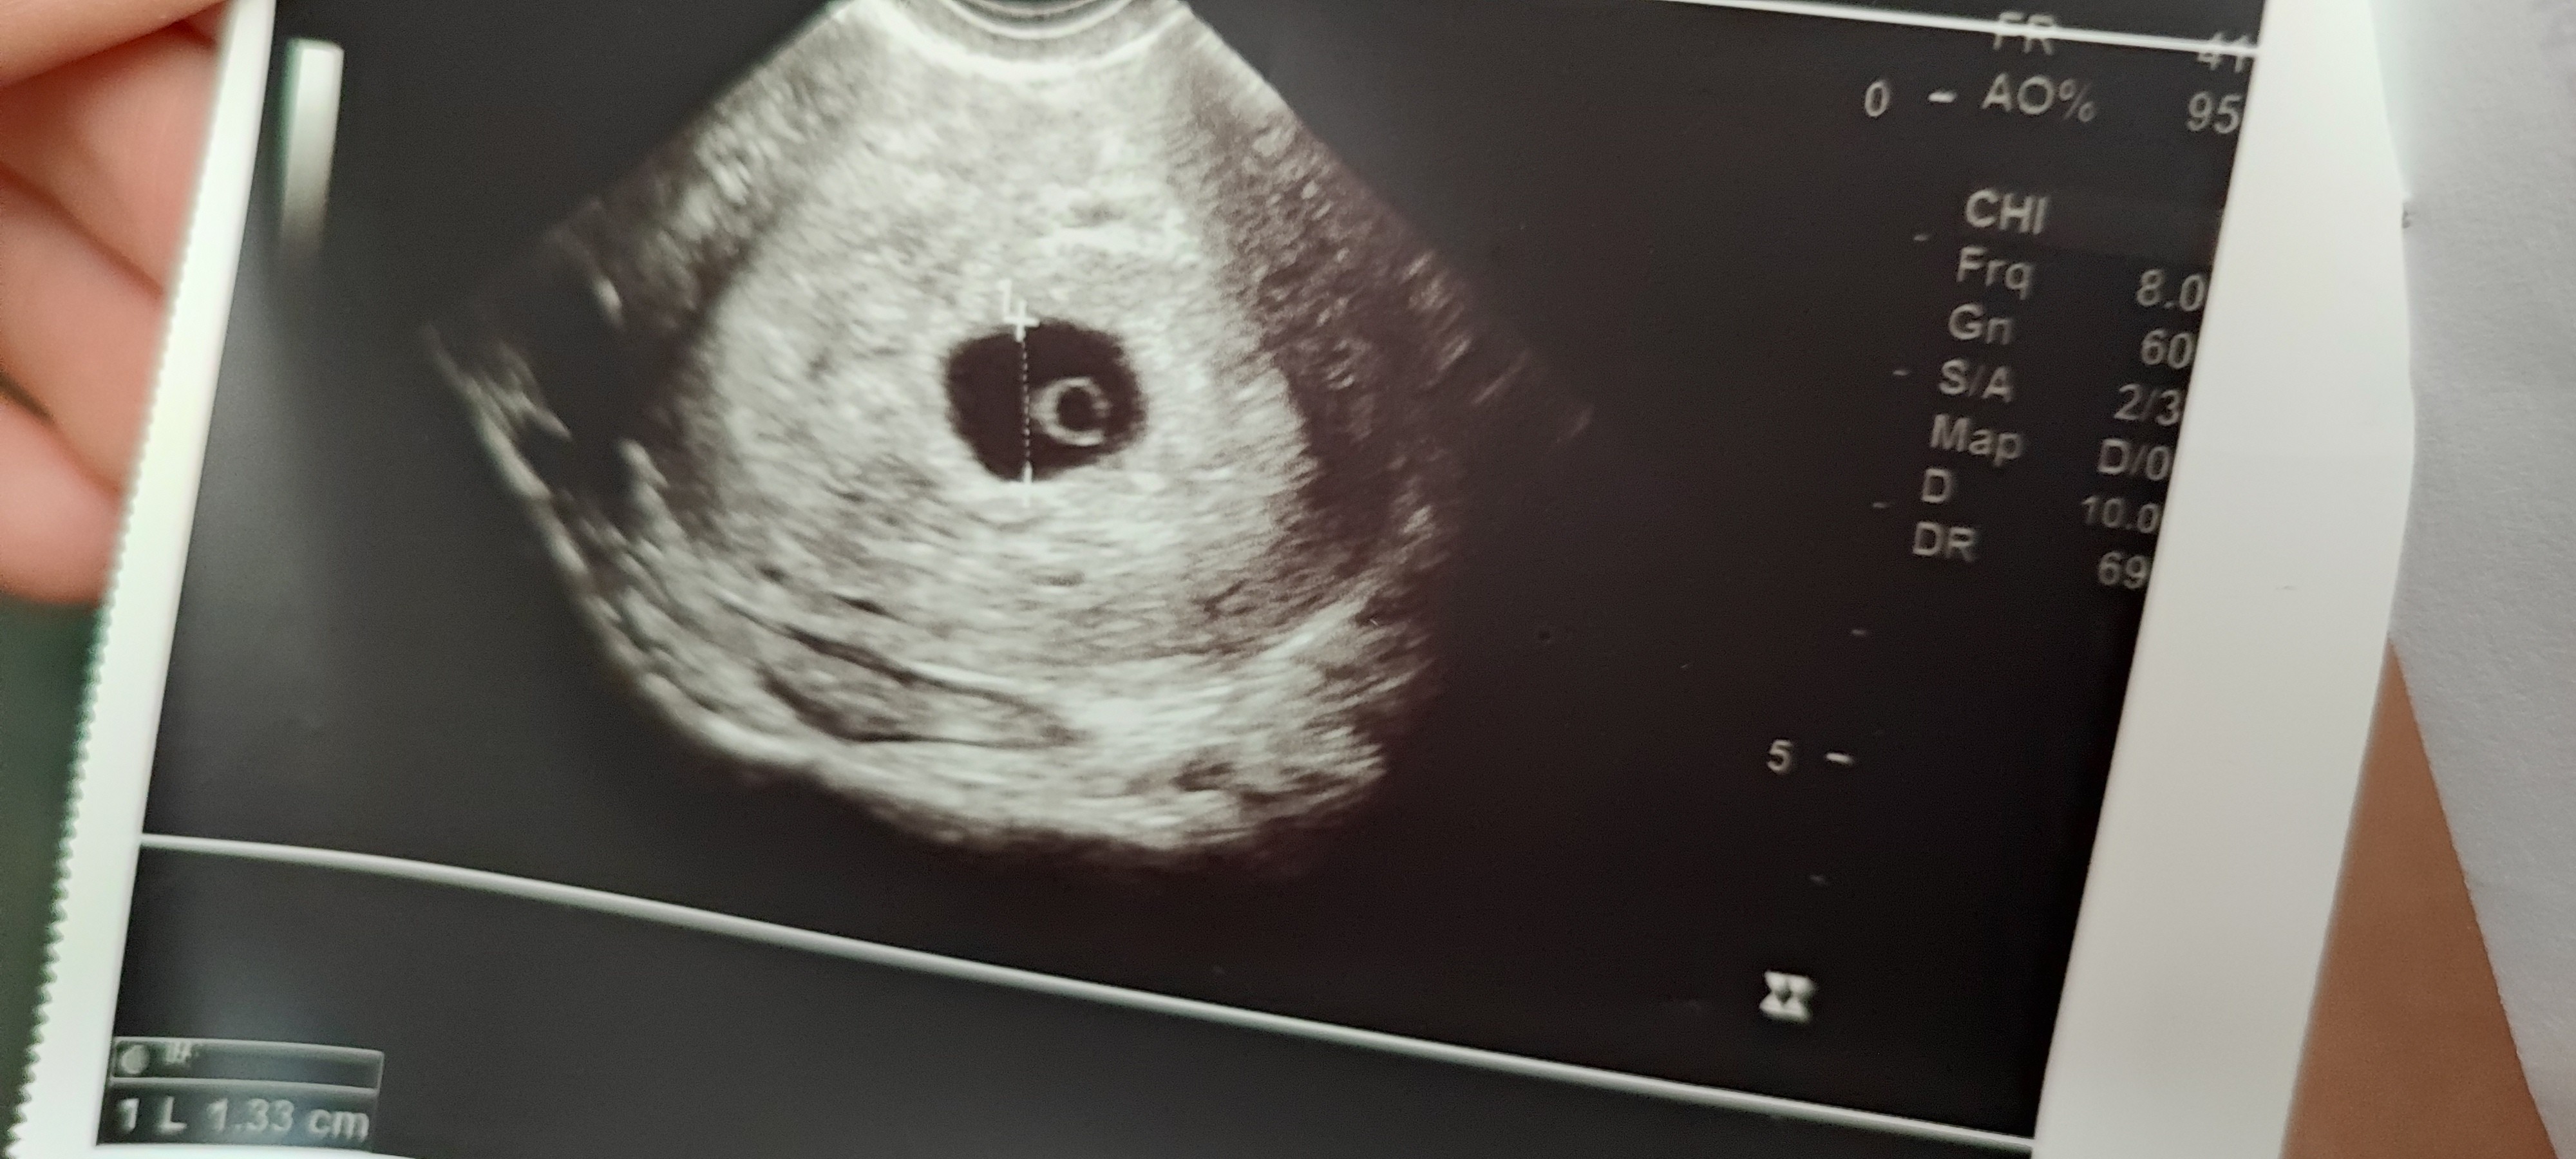

Na pierwsze USG poszłam w tamtym tygodniu w 6+2. Było widać jedynie pęcherzyk ciążowy i pęcherzyk żółtkowy, bez zarodka.

Dzisiaj byłam kolejny raz na USG i niestety nadal nie ma zarodka. Lekarz twierdzi że jeszcze jest szansa i zarodek może się jeszcze pojawić bo nie widzi żadnej patologii.

Jestem po poronieniu w maju, wtedy pęcherzyk żółtkowy był ogromny i od pierwszego USG wiedziałam że będzie źle, a teraz już sama nie wiem co myśleć.Zobacz załącznik 1654468

Byłam dzisiaj na USG, 8+2. Pęcherzyk żółtkowy urósł do gigantycznych rozmiarów, ma 9mm, pojawił się jakiś malutki zarodek ale bez akcji serca. Czekam na poronienie, jeśli nie zacznie się samo za tydzień szpital.